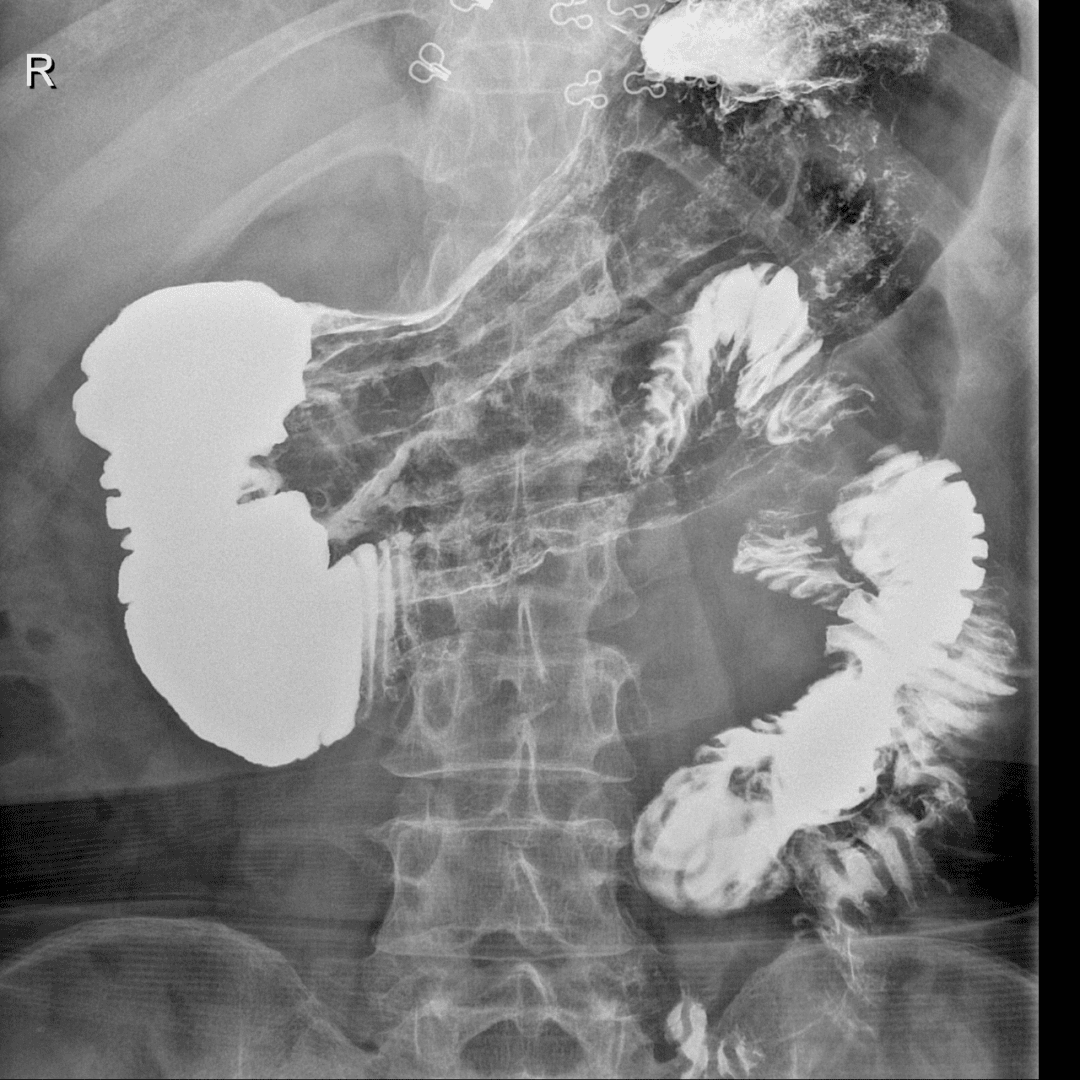

辅助检查:血、大小便及心电常规正常。免疫过筛、肝功能等正常。上腹部CT平扫未见异常。纤维胃镜示表浅性糜烂。上消化道气钡双重造影示:食管、胃腔、十二指肠上段、降段显影正常。十二指肠水平部造影剂停滞不前,呈“笔杆”状截断,改变体位后,胃腔蠕动数次后造影剂迅速通过水平部截断处。

上消化道气钡双重造影为主要诊断方法。初次超声及CT检查无器质性病变容易漏诊,针对性测量肠系膜上动脉与腹主动脉夹角(<20°,正常为40°~60°)可明确诊断。